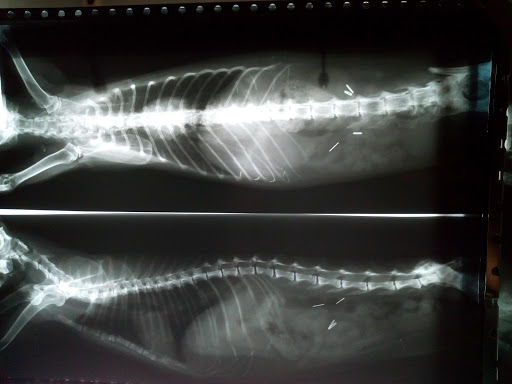

El Centro Veterinario Cedeira es un negocio dedicado a la atención y cuidado de mascotas, ubicado en Camiño Real da Magdalena, 11 en Cedeira. Con una amplia experiencia en el sector, este centro se ha convertido en …